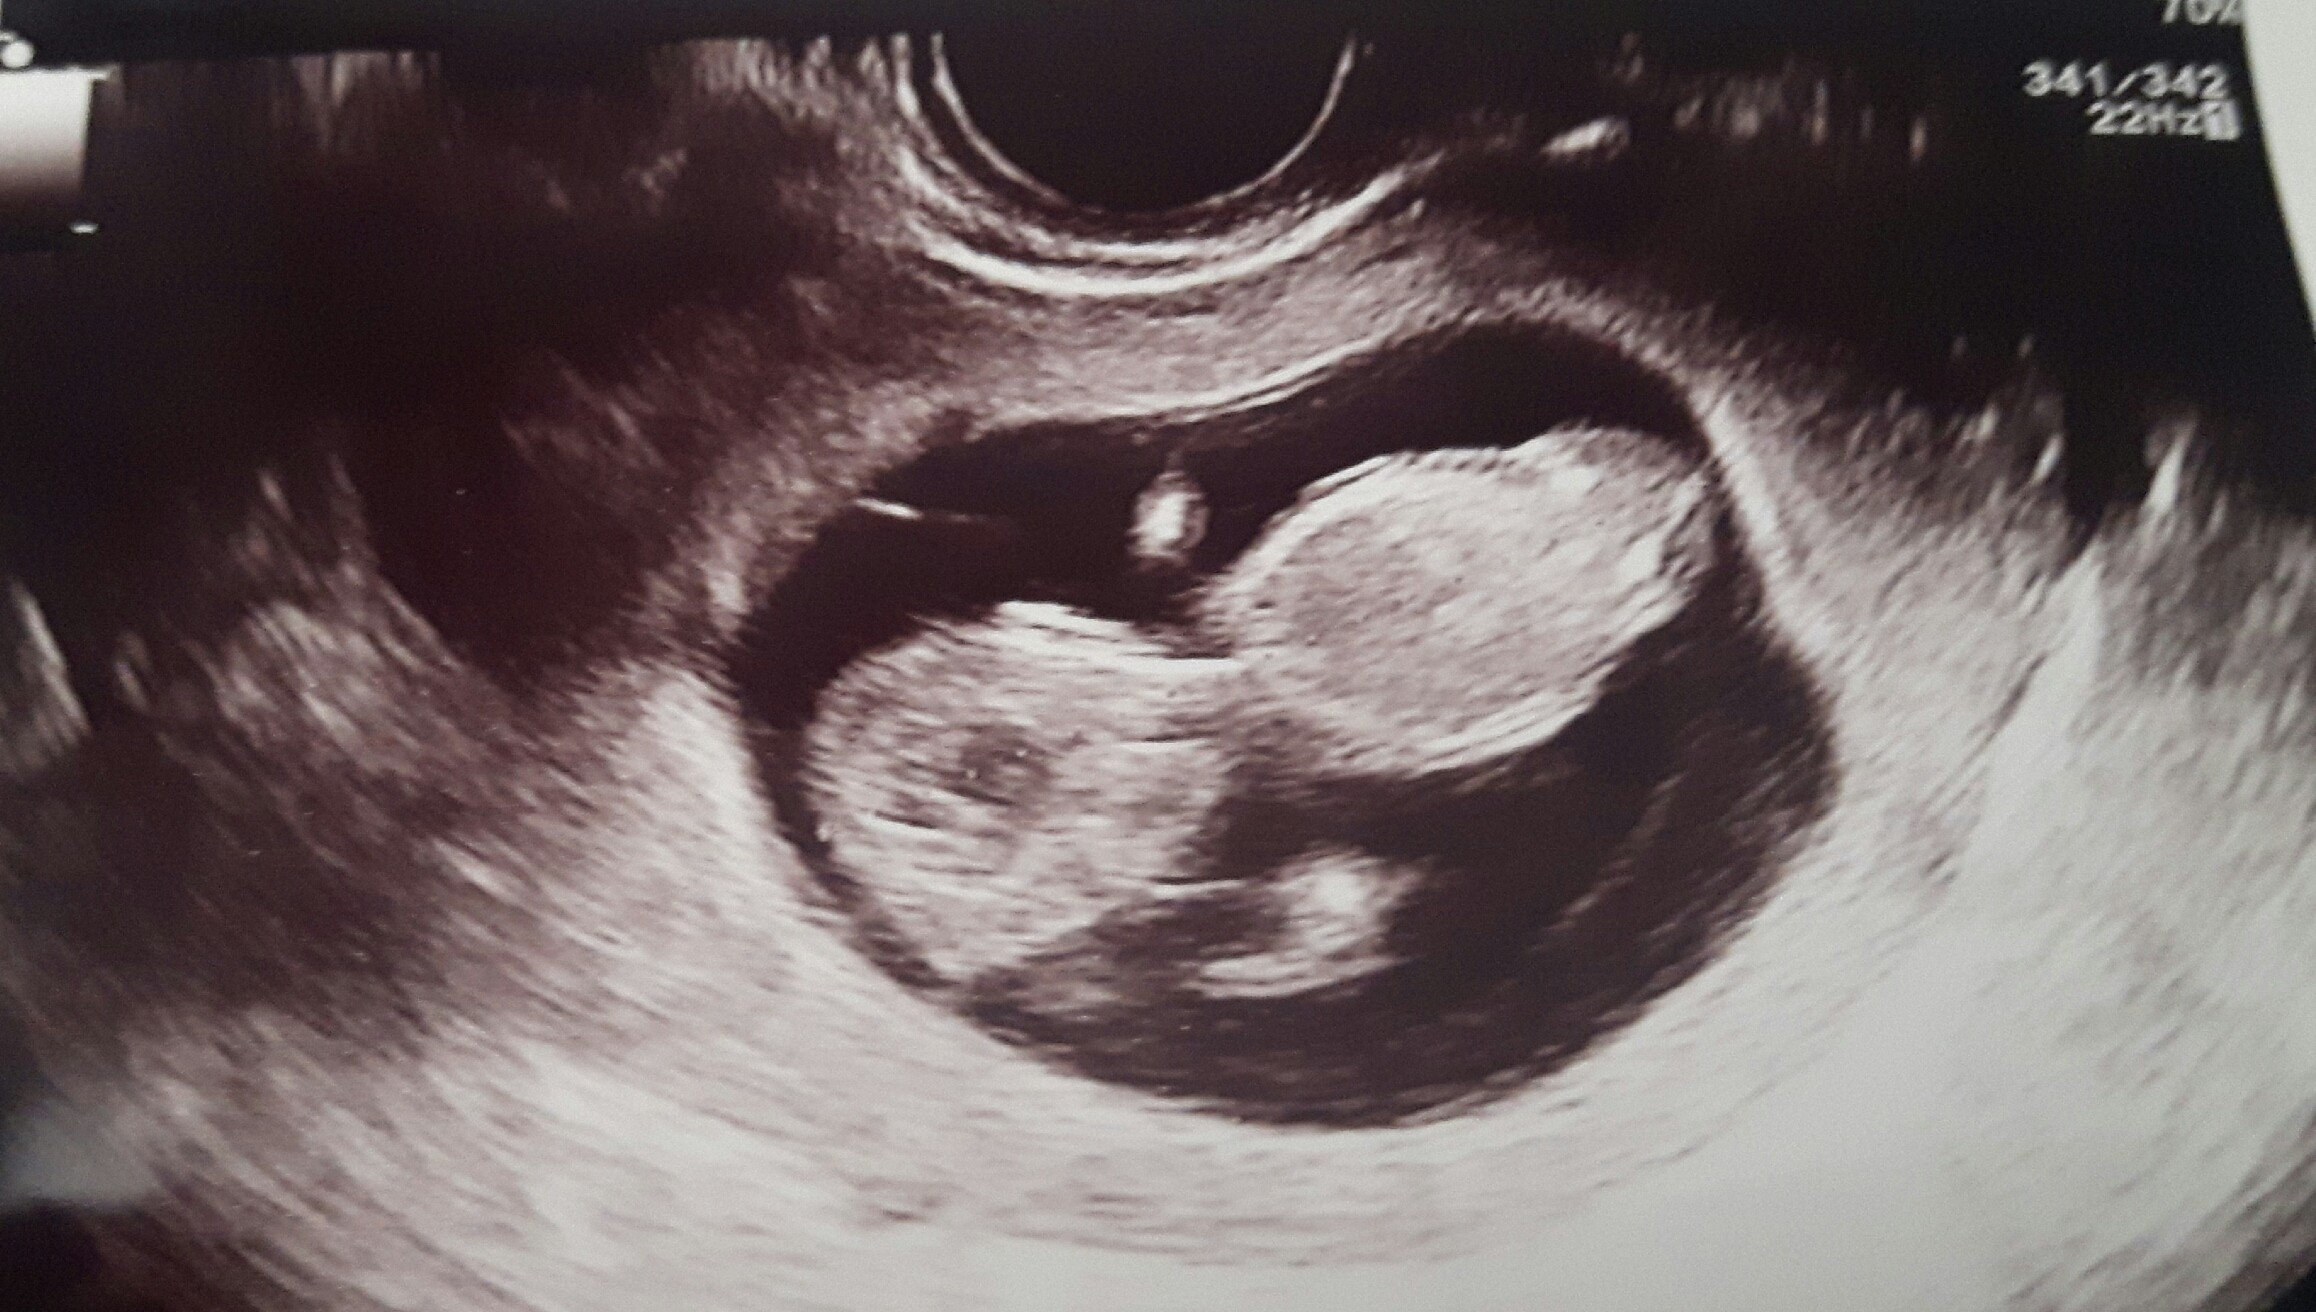

Jestem właśnie po wizycie. Wszystko super, mam pozwolenie na szaleństwa podczas sobotniego wesela kuzynowstwa. :)

Zobacz załącznik 883035

CRL 4.46 cm

Wg OM: 11 + 3

Wg USG: 11 + 2

Serducho: 160

Termin OM: 15.02.2019

Termin USG: 16.02.2019

Widać jak Maleństwo się rusza na USG, meeega aktywne. :)

Teraz czekam na prenatalne 9 sierpnia. A kolejna "ciążowa" wizyta u mojego ginekologa 20 sierpnia.